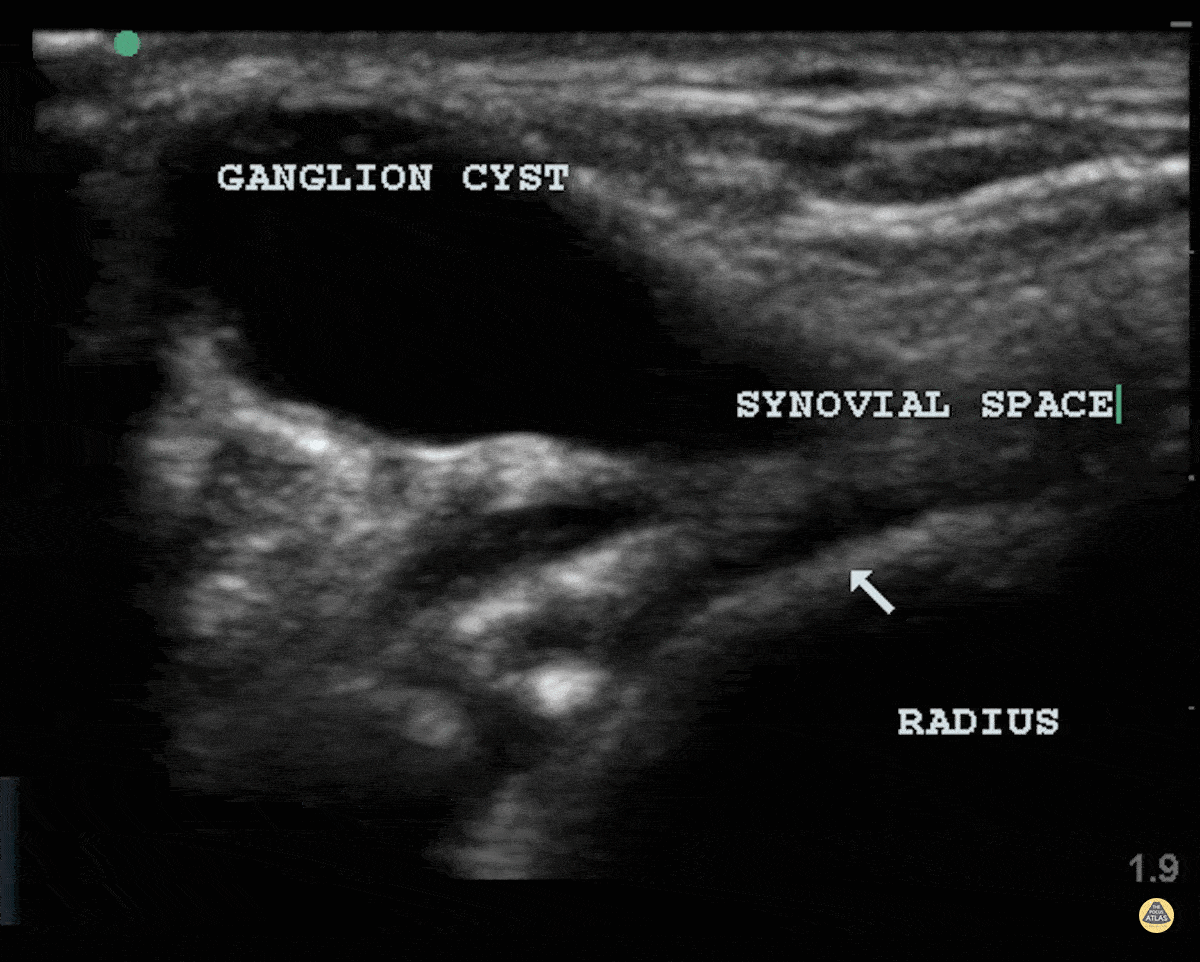

Musculoskeletal - Ganglion Cyst

Patient struck his wrist several days ago and noted a deformity. There is a clear cystic structure with no doppler flow diving between the bones and involving the synovium representing a ganglion cyst. Dr. Dustin Morrow